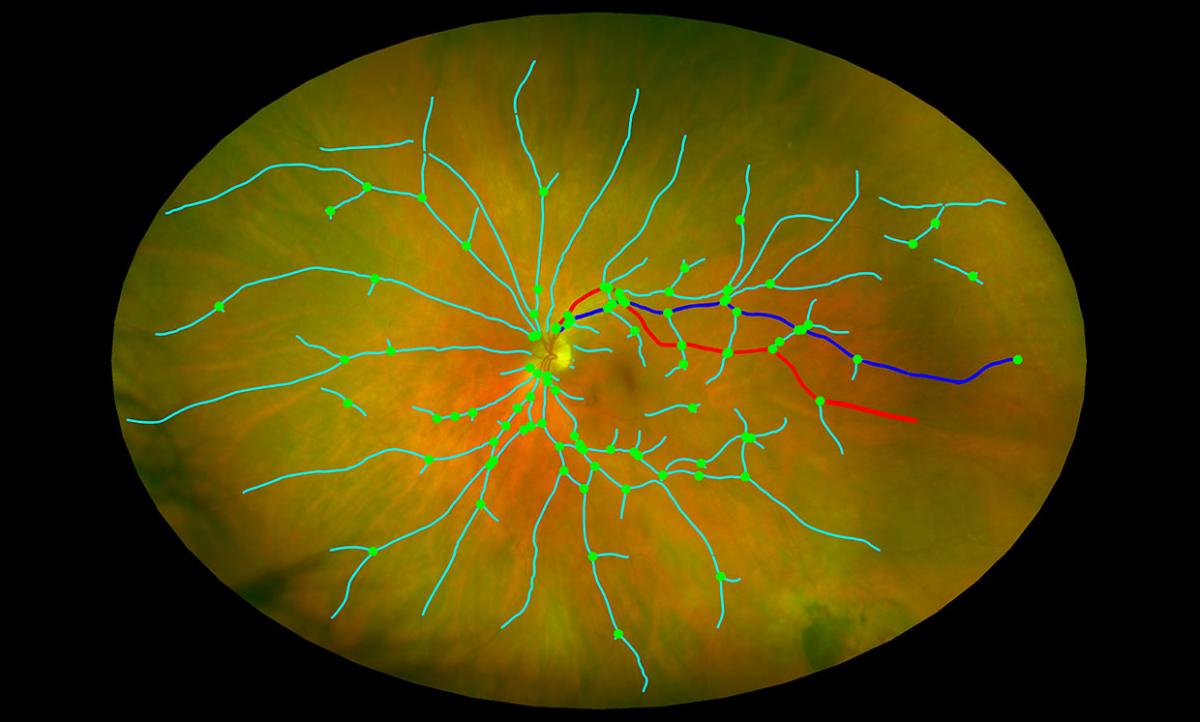

Одним из них может стать сетчатка глаза пациента. Она является одним из самых перспективных биомаркеров для ранней диагностики болезни Альцгеймера, а тест можно провести в кабинете офтальмолога без предварительной подготовки. Оказывается, по неровностям слоев сетчатки можно определить стадию заболевания, при этом анализ проводится искусственным интеллектом в течение нескольких минут.

Например, платформа компании Optina Diagnostics использует искусственный интеллект для анализа гиперспектральных изображений сетчатки, полученных с помощью специальной камеры (Metabolic Hyperspectral Retinal Camera, MHRC) во время простого сканирования глаз. Устройство записывает непрерывный спектр длин волн, который может быть проанализирован для определения наличия определенных биомаркеров, таких как бета-амилоидные бляшки, которые считаются признаками болезни Альцгеймера. Новая система, как утверждают специалисты Optina, будет недорогостоящей и существенно более доступным средством для скрининга, чем большинство существующих сегодня методик.

В свою очередь ученые из Эдинбургского университета разрабатывают комплексную систему сканирования глаз, анализирующей многочисленные биомаркеры в глазах для выявления дегенерации мозга. Программное обеспечение для анализа изображений с компонентами машинного обучения, позволяет анализировать изображения, полученные с помощью оборудования для сканирования глаз, которое уже имеется в офисах врачей-офтальмологов. Система позволяет измерять изменения малых кровеносных сосудах в задней части глаза и изменения в слоях нервной ткани глаза, которые связаны с болезнью Альцгеймера и предшествуют серьезным симптомам когнитивного упадка, проявляющимся позднее.